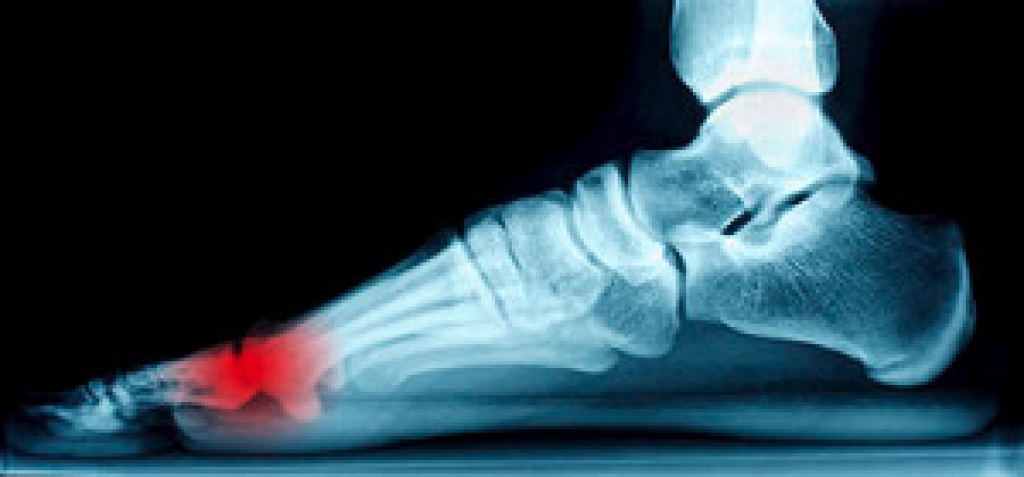

Patients who stub their toe against a piece of furniture, or drop a heavy object on it, may experience a broken toe. The average healing time for this type of injury is generally four to six weeks, and it is often accompanied by swelling and bruising. Additional symptoms can include severe pain and it may be difficult to put a shoe on and walk. Mild relief can be found if you have a mildly fractured toe by taping the affected toe to the toe next to it. This is referred to as buddy taping, and it is typically effective in providing the necessary stability to the affected toe as the healing process occurs. Severely broken toes may require that a cast be worn, and it can be helpful to use crutches to keep weight off of the toe. If you have fractured your toe, please consult with a podiatrist.

A broken toe occurs when one or more of the toe bones of the foot are broken after an injury. Injuries such as stubbing your toe or dropping a heavy object on it may cause a toe fracture.